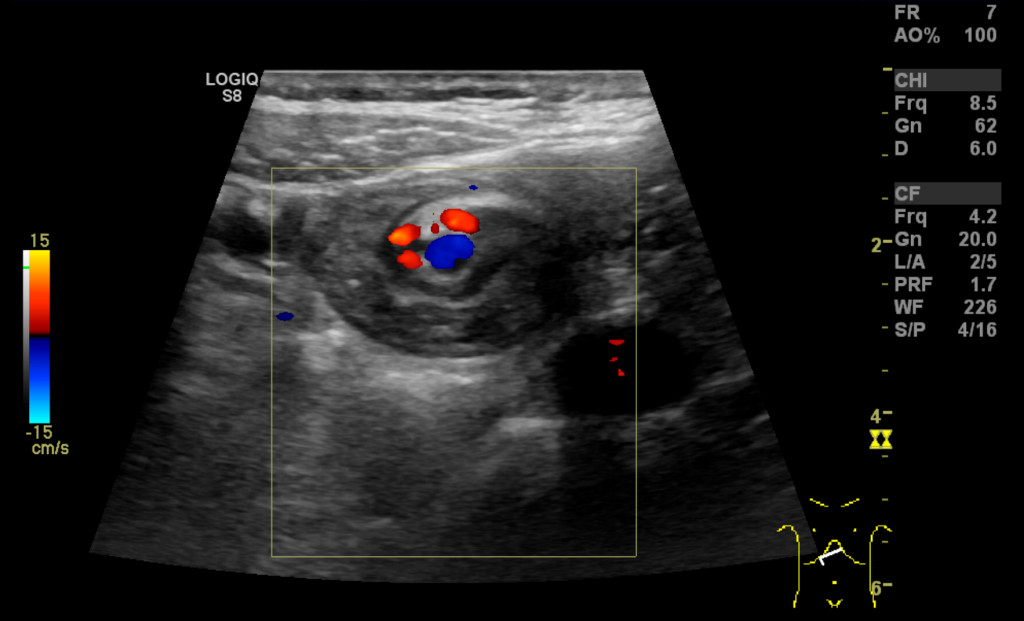

Such a pronounced and acute exacerbation was not consistent with previously considered diagnoses such as abdominal migraine, gastroesophageal reflux and constipation; gastric retention and superior mesenteric artery syndrome were therefore considered as alternative differential diagnoses. Upon admission, treatment was started with erythromycin (Ery-Max) suspension 3 mg/kg to stimulate gastric emptying, intravenous NaCl and glucose solution with added sodium and potassium, and potassium suspension 10 ml x 3 orally. Abdominal ultrasound was performed on Friday evening by a specialty registrar in radiology, who described a whirl sign in the epigastrium involving the superior mesenteric artery and vein (Figure 1). The doctor suspected intestinal malrotation and recommended, in the first instance, a confirmatory ultrasound by an experienced paediatric radiologist in daytime hours. An acute angle was also noted between the aorta and the proximal portion of the superior mesenteric artery, consistent with possible superior mesenteric artery syndrome. Abdominal x-ray showed normal findings.

Figure 1 Ultrasound. Whirl sign involving vessels and the small intestine in the epigastrium.

The girl was kept under observation throughout the weekend. Her general condition had improved, and she had little abdominal pain and no episodes of vomiting. Her electrolyte levels quickly normalised following initiation of fluid therapy. On Monday morning, an ultrasound examination was performed by an experienced paediatric radiologist who confirmed the whirl sign (Figures 1 and 2) and who suspected concomitant volvulus (where a loop of intestine twists about its own axis). The diagnosis was confirmed by an upper gastrointestinal series, which showed passage of contrast to the proximal small intestine, but no further (Figure 3). The transition between the duodenum and small intestine was just to the left of the midline, caudal to the level of the duodenal bulb, which suggested malrotation with volvulus. The explanation for the patient's long-term symptoms had finally been found (Figure 4).

Figure 2 Ultrasound. Whirl sign involving mesenteric vessels and loops of small intestine. The superior mesenteric artery …

Figure 2 Ultrasound. Whirl sign involving mesenteric vessels and loops of small intestine. The superior mesenteric artery (red Doppler signal) is to the right of the superior mesenteric vein (blue Doppler signal).

Upon ultrasound examination, the superior mesenteric vein can usually be seen to the right of the superior mesenteric artery. If the vein is to the left or in front of the artery, this should raise strong suspicion of malrotation. Sensitivity is reported to be 67–100 % and specificity 83–92 % (7). If abnormal positioning is detected with ultrasound, an upper gastrointestinal series should then be performed. In our patient, ultrasound revealed the 'whirl sign', which is considered 100 % specific for midgut volvulus (7): the duodenum, the proximal portion of the small intestine, and the superior mesenteric vein twist around the superior mesenteric artery. The underlying cause is malrotation and a short mesentery. Midgut volvulus gives rise to a duodenal – i.e. proximal – obstruction, and abdominal x-ray may thus be completely normal, despite the child having an acute condition in need of surgical intervention.